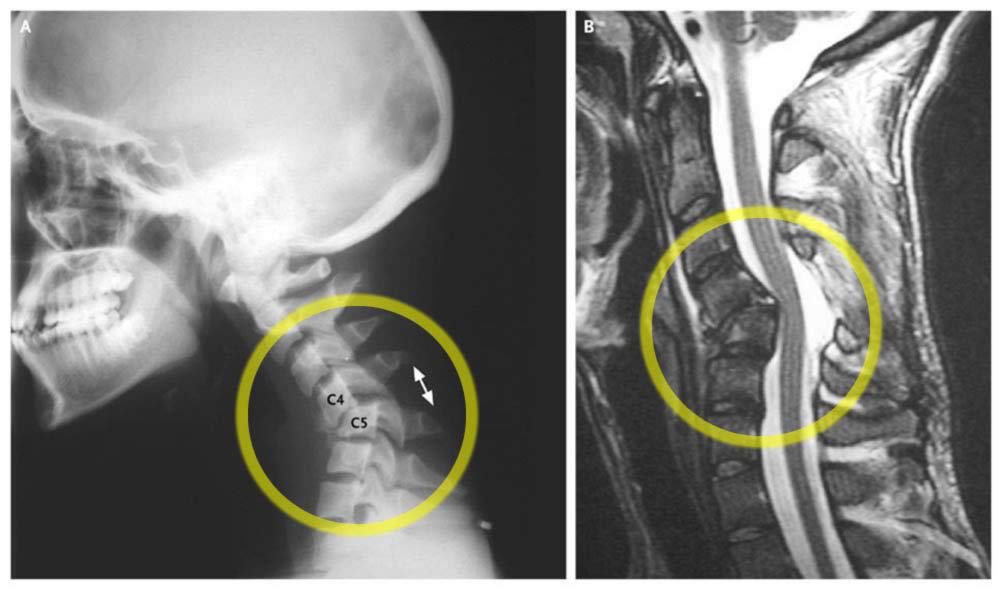

Хотя это не тот вид «подвывиха», о котором идет речь в этой статье, такие случаи действительно дают важную перспективу, поскольку истинный вывих может протекать бессимптомно, как это ни удивительно. Есть много случаев травм и фактического смещения позвонков, которые вызывают мало беспокойства или вообще не вызывают (или, по крайней мере, гораздо меньше, чем ожидает большинство людей). В учебном пособии по болям в пояснице я описываю одну из своих бывших пациенток, прошедшую курс массажной терапии [19], с очень серьезным вывихом поясничного отдела позвоночника, но без болей в пояснице (ко мне она обратилась из-за проблемы с ногой). Другой пациент с крайней степенью сколиоза, хотя и испытывал часто дискомфорт, в целом чувствовал себя удивительно хорошо и даже был в хорошей физической форме. Пациент, изображенный на фотографии, как сообщается в New England Journal of Medicine, не испытывал «боли, слабости или парестезии»! [20]

photo_2025-08-15_15-49-31.jpgТравматический вывих. Для наглядности приведен пример позвоночника, который действительно «вышел из строя». Несмотря на серьезный вывих, пациент был вполне здоров. См. статью Akhaddar